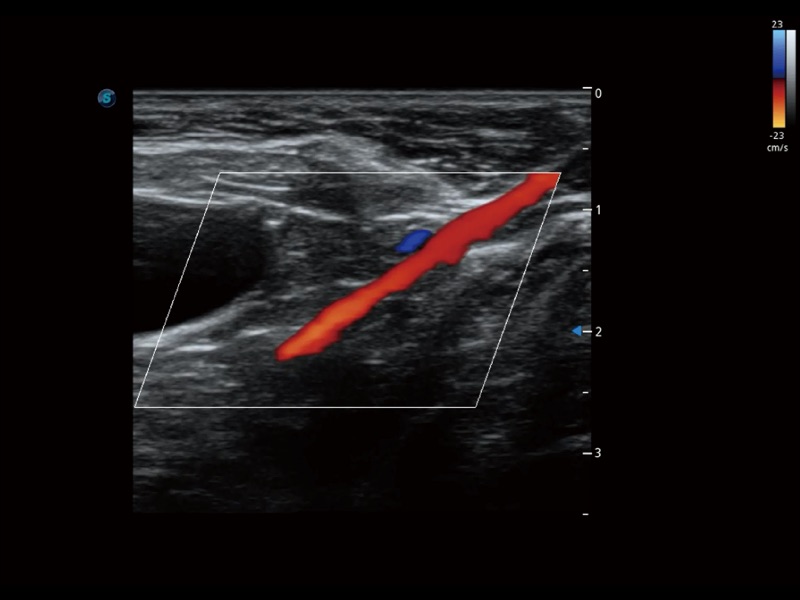

通過(guò)創(chuàng)新的 Matrix E自適應(yīng)濾波器和超長(zhǎng)時(shí)間域算法,極大提升超低速微細(xì)血流的檢出能力,同時(shí)更精準(zhǔn)地濾除軟組織和噪聲信號(hào),為獸用醫(yī)生提供以往無(wú)法通過(guò)常規(guī)血流獲得的疾病診斷信息。

通過(guò)色彩血流和實(shí)時(shí)寬景相結(jié)合,可觀察到完整的靜脈或動(dòng)脈的血流,方便醫(yī)生檢查。實(shí)時(shí)掃查過(guò)程中,如有任何操作失誤也可以很容易地進(jìn)行回掃擦除,而不會(huì)中斷掃查。

采用紅、橙、黃、綠、青、藍(lán)、紫這七種肉眼最為敏感的色彩,直觀地顯示組織內(nèi)血流灌注的時(shí)間先后信息,更精準(zhǔn)捕捉血流灌注走行細(xì)節(jié)。